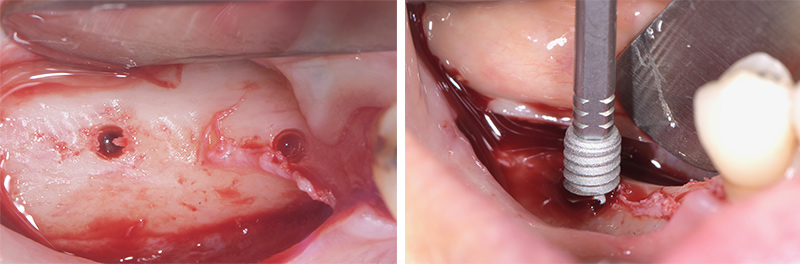

Fig. 09 : puits de forage et insertion de l’implant.

Fig. 10 : implants en place, membrane Mucoderm (Botiss).